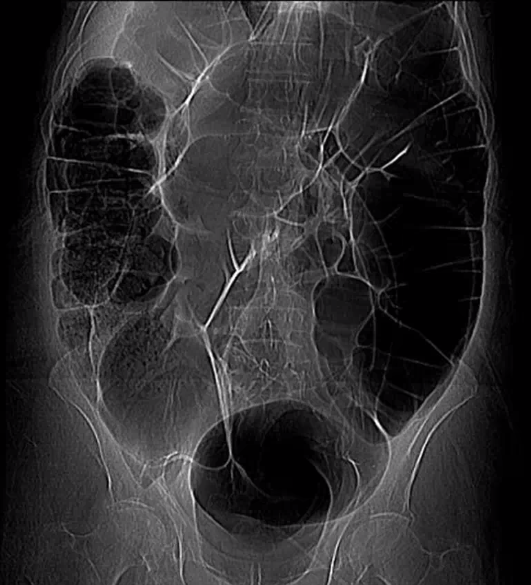

what is the pathology here?

type of imaging modality

SBO obstruction

AXR